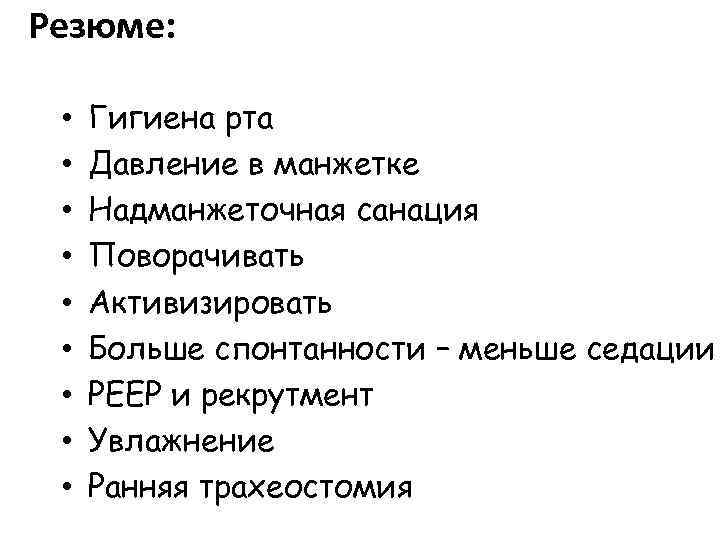

Резюме: • • • Гигиена рта Давление в манжетке Надманжеточная санация Поворачивать Активизировать Больше спонтанности – меньше седации РЕЕР и рекрутмент Увлажнение Ранняя трахеостомия

Резюме: • • • Гигиена рта Давление в манжетке Надманжеточная санация Поворачивать Активизировать Больше спонтанности – меньше седации РЕЕР и рекрутмент Увлажнение Ранняя трахеостомия

Резюме: • • • Гигиена рта Давление в манжетке Надманжеточная санация Поворачивать Активизировать Больше спонтанности – меньше седации РЕЕР и рекрутмент Увлажнение Ранняя трахеостомия

Резюме: • • • Гигиена рта Давление в манжетке Надманжеточная санация Поворачивать Активизировать Больше спонтанности – меньше седации РЕЕР и рекрутмент Увлажнение Ранняя трахеостомия